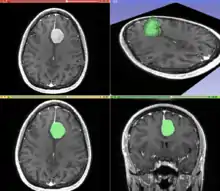

Information can take the form of images, sound, video or other multimedia. Bits of information can be streamed via signals. Its processing is the central notion of informatics, the European view on computing, which studies information processing algorithms independently of the type of information carrier – whether it is electrical, mechanical or biological. This field plays important role in information theory, telecommunications, information engineering and has applications in medical image computing and speech synthesis, among others. What is the lower bound on the complexity of fast Fourier transform algorithms? is one of unsolved problems in theoretical computer science.

| FFT algorithms | Image processing | Speech recognition | Data compression | Medical image computing | Speech synthesis |